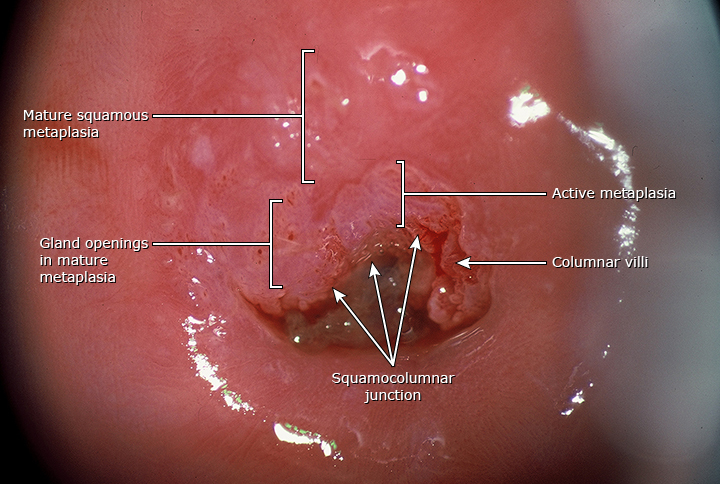

女性尿道口对称肉芽

常见于青春期以后的青少年,妊娠女性和使用含有雌激素避孕用品的女

前庭位于尿道口和阴道口外延的一整片菱形区域,由小阴唇围成.